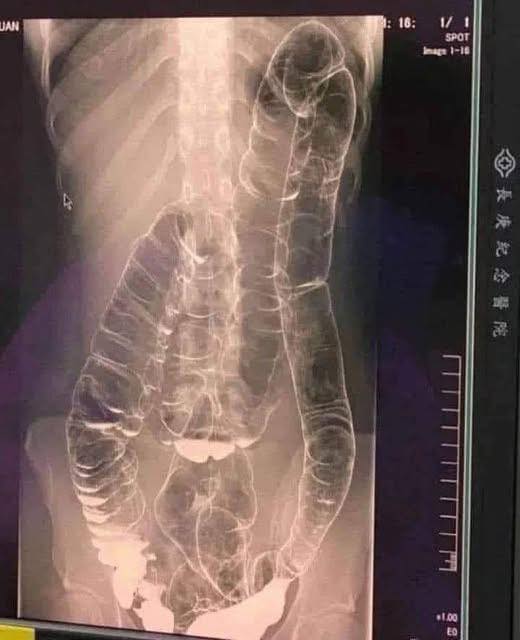

Immaginate di rimanere più di due settimane senza evacuare… È quanto accaduto a una giovane il cui colon è risultato dilatato a causa di un tale accumulo.

- Distensione del colon: perde elasticità e diventa sempre meno efficiente.